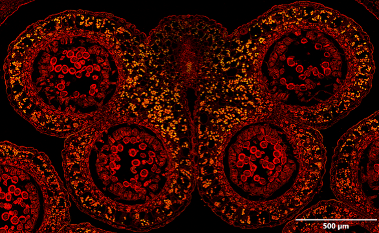

The figure presents an example of selective detection performed using a neural network trained to identify pancreatic islets (PIs). a) Overview of a rat pancreas section stained with fluorescent labels (Alexa Fluor 594, shown in yellow) at 4X magnification. b) and c) Higher-magnification images of two pancreatic islets. d) Final scans (DAPI in blue and Alexa Fluor 594 in yellow) superimposed on the overview image. Only two regions containing pancreatic islets were rescanned at higher magnification (40X).